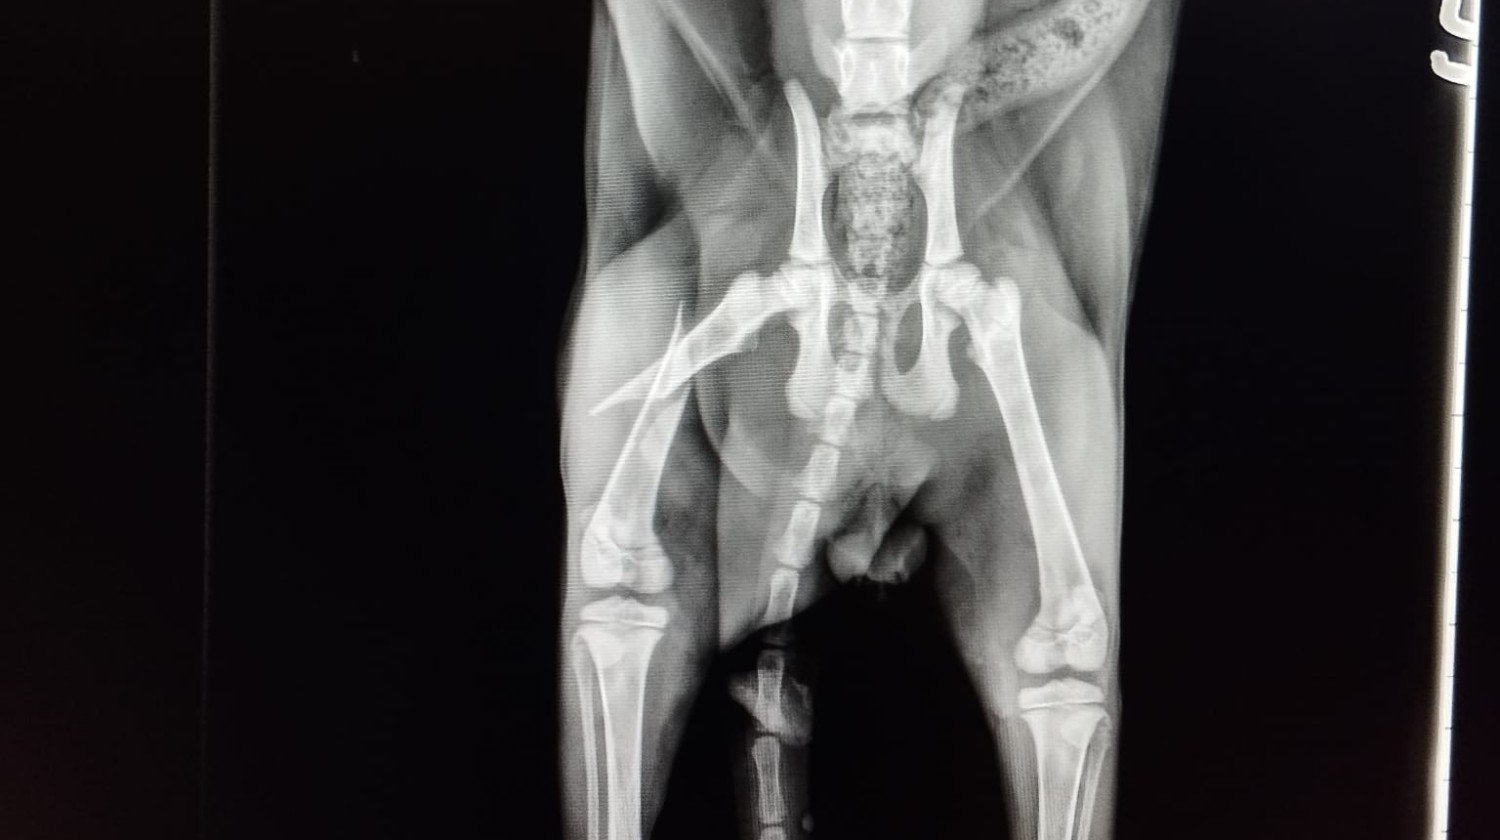

Prosimo za pomoč pri operaciji dvomesečnega mačka, ki si je zlomil stegnenico in potrebuje nujno operacijo.Stroški operacije so zelo visoki.Hvaležni vam bomo za vsako donacijo.Najlepša hvala.